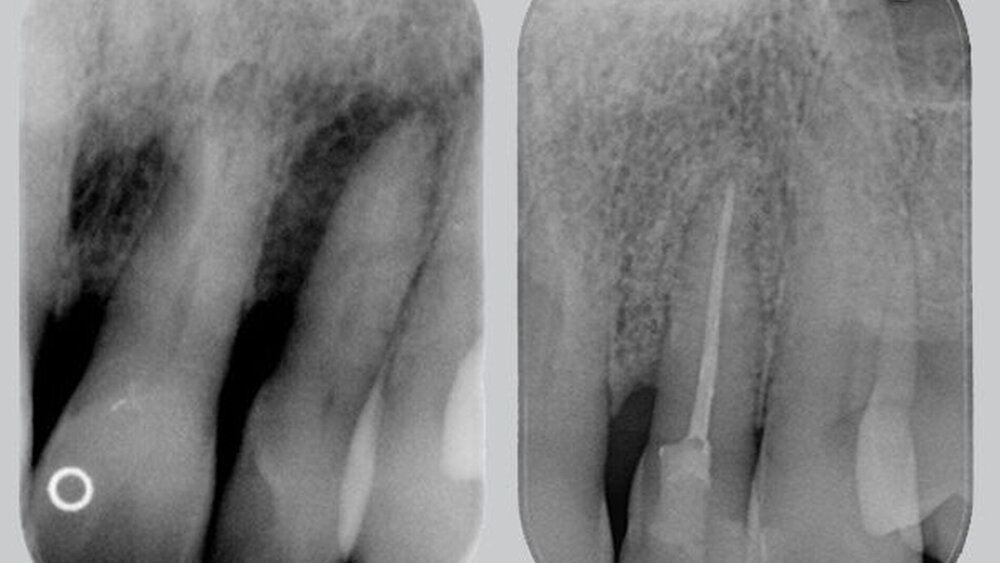

Nach Durchführung der nicht-chirurgischen Parodontitisbehandlung im Rahmen der systematischen Parodontitistherapie fanden sich bei Reevaluation im Juni 2013 noch lokalisiert vertiefte Sondierungstiefen an einzelnen Zähnen, unter anderem an Zahn 22 mit 12mm und Bleeding on Probing (BOP). Ein vertikaler Knochendefekt konnte im Röntgenbild diagnostiziert werden (Abbildung 3), woraufhin ein regeneratives parodontal-chirurgisches Verfahren an diesem Zahn geplant wurde.

Im Rahmen der Lappenoperation im Januar 2014 wurde ein knöcherner Defekt bis um den Apex festgestellt (Abbildung 4). Die Prognose des Zahns wurde daher mit einem Knochenabbau von 100 Prozent als hoffnungslos eingestuft [Checchi et al., 2002]. Dennoch wurde nach Rücksprache mit dem Patienten von einer Extraktion abgesehen und im Rahmen eines Erhaltungsversuchs das geplante regenerative Verfahren fortgesetzt.

Nach Glättung der Wurzeloberfläche und kompletter Entfernung des Granulationsgewebes wurde der Defekt mit einem Knochenersatzmaterial bovinen Ursprungs gefüllt und mit einer resorbierbaren Kollagenmembran abgedeckt. Der Nahtverschluss erfolgte mit einem nicht-resorbierbaren Nahtmaterial (Größe 610). Aufgrund des Ausmaßes des Knochendefekts um den gesamten Apex wurde direkt im Anschluss eine Wurzelkanalbehandlung durchgeführt sowie eine semipermanente Schienung mittels Composite (Abbildung 5). Kontrollen fanden ein und zwei Wochen nach der parodontal-chirurgischen Therapie statt. Die Entfernung der Nähte erfolgte zwei Wochen post operationem.